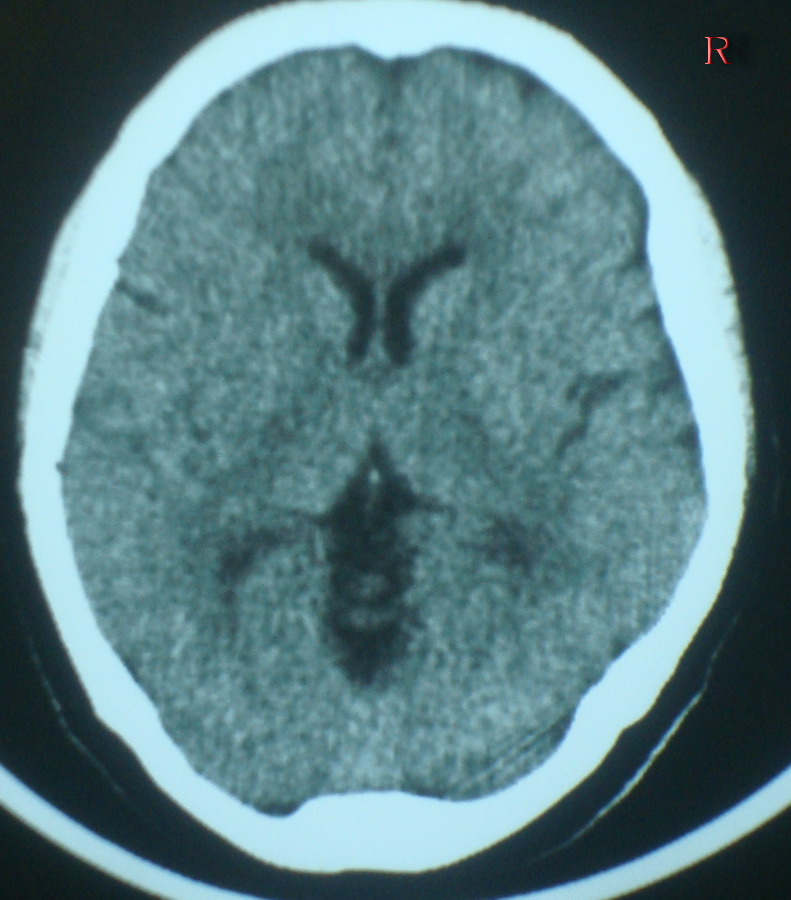

标题: CT19025:女,60岁,突感头痛,忘事两天 [打印本页]

标题: CT19025:女,60岁,突感头痛,忘事两天

右侧颞顶叶交界区片状低密度灶;建议行进一步检查。

以下是引用随光逐影在2009-3-25 21:14:00的发言:[br]右侧颞顶叶交界区片状低密度灶;建议行进一步检查。

右侧颞顶叶交界区片状低密度灶;建议行进一步检查。-----支持!

右侧颞顶叶交界区片状低密度灶;建议行进一步检查.